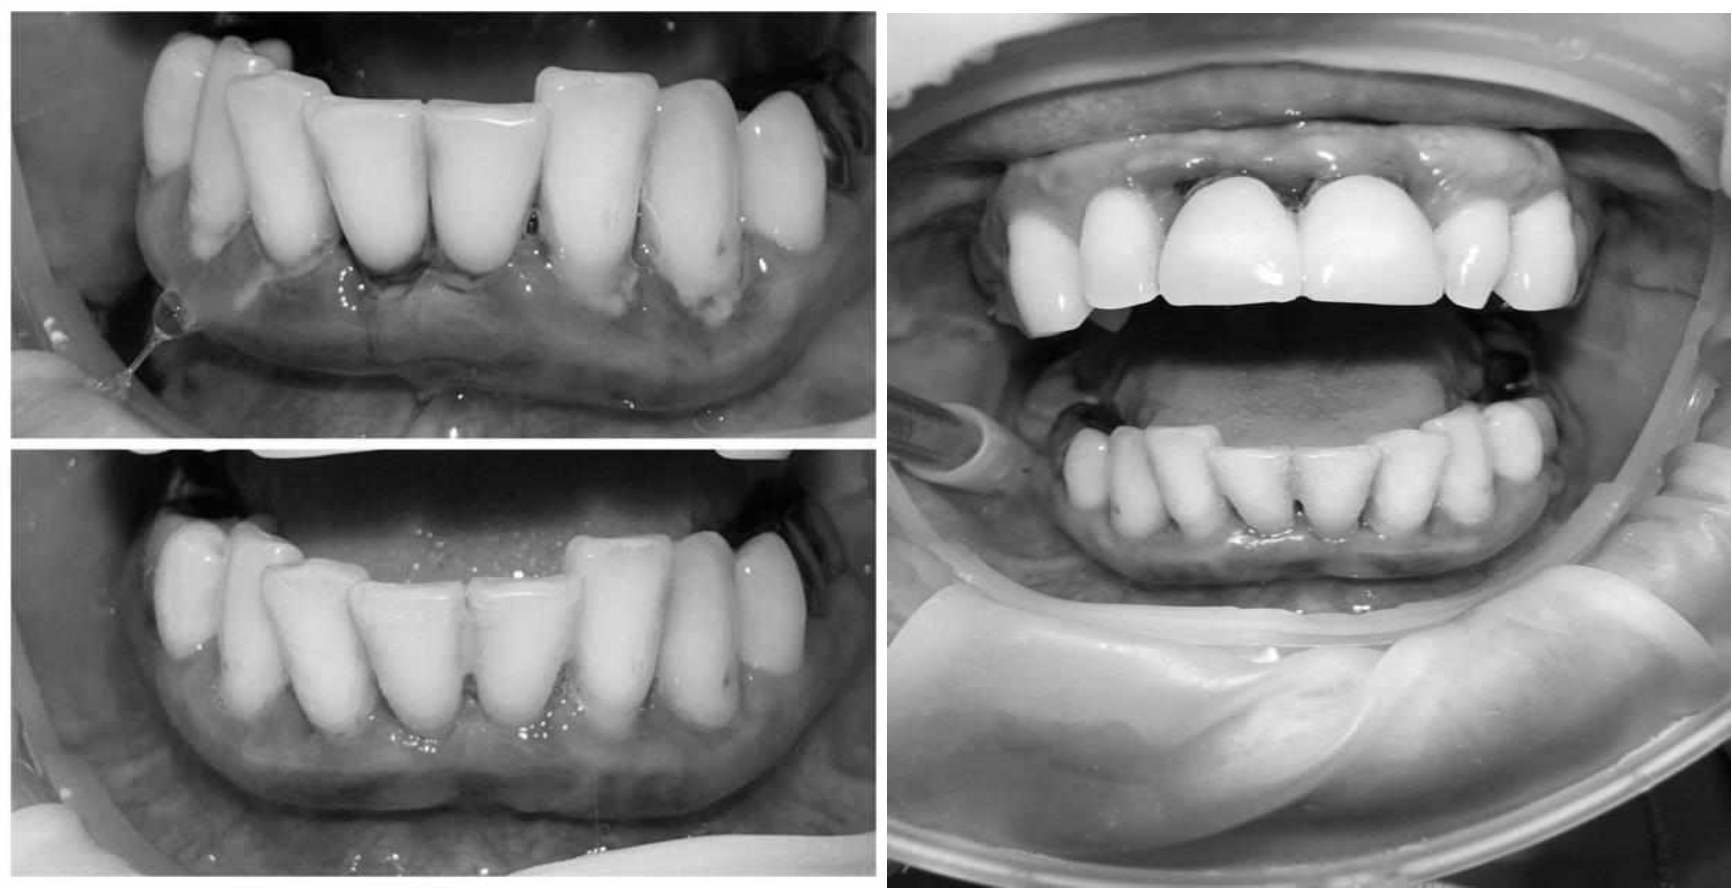

Ранее у пародонтолога не наблюдалась. При осмотре выявлены: неудовлетворительная индивидуальная гигиена полости рта, пародонтальные карманы до 7 мм, обильная кровоточивость и гноетечение из пародонтальных карманов, подвижность зубов 4.2, 4.1, 3.1, 3.2 II степени, обильные над- и поддесневые зубные отложения (рис. 1). На ортопантомограме отмечается резорбция костной ткани до ½ длины корня, очаги остеопороза (рис. 2). Пациенту был поставлен диагноз хронический генерализованный пародонтит тяжелой степени тяжести. При осмотре была составлена пародонтограмма с использованием компьютерного зондирования (рис. 3).

Рис. 1. Внешний вид

Через 6 месяцев при осмотре выявлен удовлетворительный уровень индивидуальной гигиены, отсутствие участков кровоточивости и гноетечения (рис. 4), пародонтальные карманы уменьшились в размерах (рис. 5). Пациент отмечает значительные улучшения. После стабилизации пародонтологического статуса пациент направлен для дальнейшего ортопедического лечения.

Рис. 4. Динамика результата через 6 месяцев